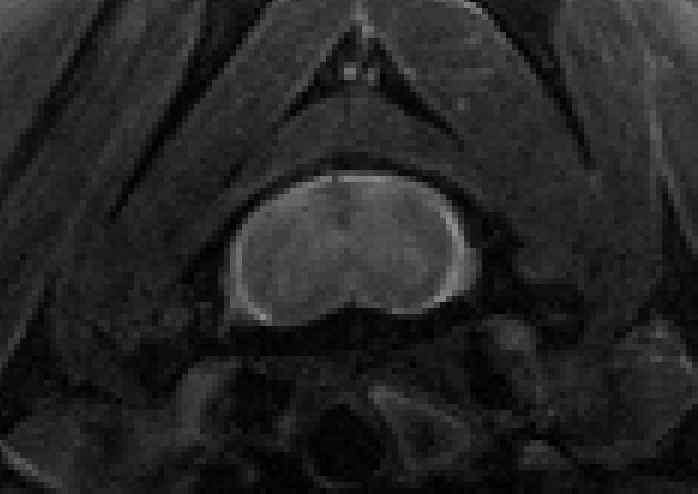

Figure 1: Image de la moelle épinière cervicale chez la souris obtenue par IRM à 9,4T